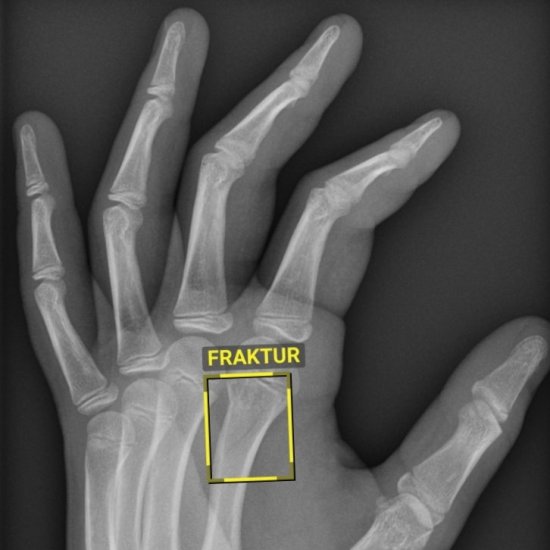

Medizinische Notfälle erfordern präzise Kommunikation, auch unter extremen Bedingungen. Forscher testeten daher auf einer simulierten Mondoberfläche Anleitungen zur medizinischen Versorgung bei einer Herzrhythmusstörung. Künstliche Intelligenz unterstützt zudem die Radiologie: An der Universitätsmedizin Göttingen markiert ein neues KI-Assistenzsystem Frakturen in Röntgenbildern innerhalb von Sekunden. In wenigen Tagen startet die MEDICA 2025; auf der Messe in Düsseldorf präsentieren hunderte Start-ups innovative Medizintechnik-Lösungen. Viel Spaß beim Lesen!

News • Interventionelle Radiologie

Frakturen in Sekunden erfassen und markieren: Ein neues KI-Assistenzsystem hilft seit Kurzem in der Radiologie der Universitätsmedizin Göttingen bei der Auswertung von Röntgenbildern. |